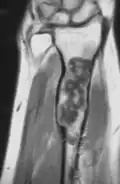

X-ray showing enchondromas localized in the lower part of the radius of a 37-year-old patient affected with Ollier disease -

MRI showing enchondromas localized in the lower part of the radius of a 37-year-old patient affected with Ollier disease -

MRI showing enchondromas localized in the lower part of the radius of a 37-year-old patient affected with Ollier disease. -